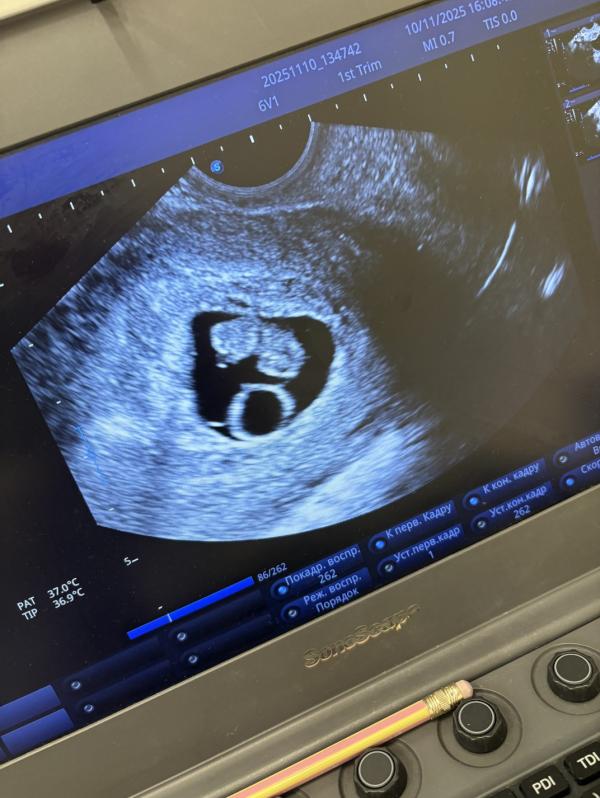

8 недель беременности: хорошее сердцебиение и нет токсикоза

По узи 8н1д

Сердцебиение хорошее 🤌🏽